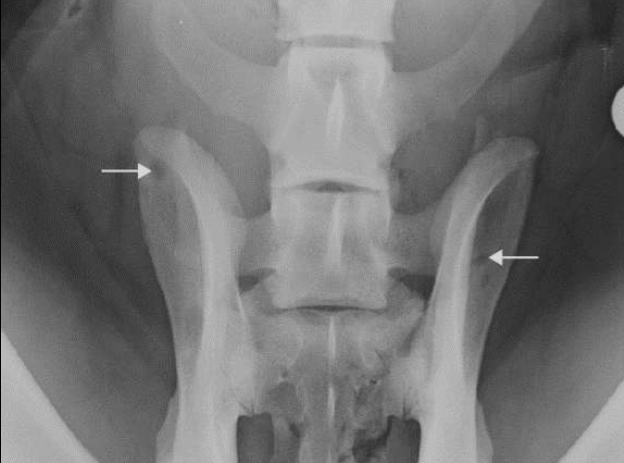

How can lesions in a bone be distributed?

Monostotic

Polyostotic

Focal

Generalized

Symmetrical

Asymmetrical